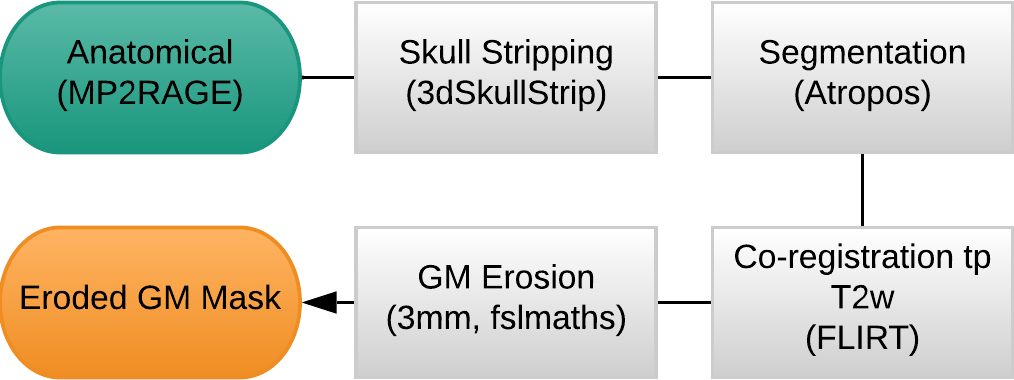

Methods: Preprocessing

- MP2RAGE and T2w skullstripped (AFNI)

- MP2RAGE normalised to MNI152 template (ANTs)

- T2w registered to MP2RAGE and to SBREF (FSL)

- MP2RAGE segmented and GM registered to SBREF (ANTs)

- GM eroded (FSL)

- EPI realigned to SBREF, saved the motion parameters (ANTs)

- EPI skullstripped (FSL)

Methods: preprocessing

Functional:

- motion realignment

- skullstripping

- optimal combination (OC)

- distortion correction

CO2 traces:

- (supervised) peak detection

- linear interpolation of peaks and convolution with HRF

- cross-correlation with average GM signal

- creation of lagged regression (range: ±9 s, step: 0.3 s)

- interpolation to fMRI TR